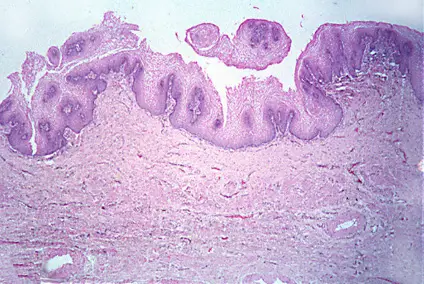

Una capa de c�lulas keratinizadas cubre la epidermis. Obs�rvese la similitud entre el espesor del epitelio de la vagina (abajo) y la epidermis (arriba)

Epitelio vaginal